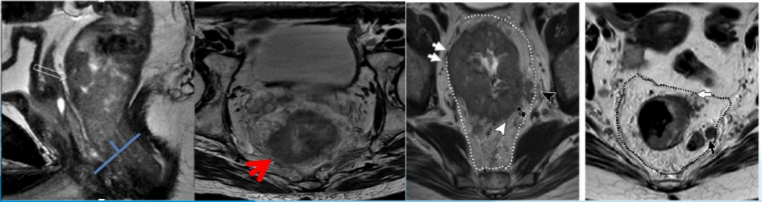

首先进行矢状位定位扫描,在肿瘤层面设计与直肠壁垂直的横断位图像 (蓝线),冠状位图像定位垂直于横断位 (黄线)

矢状面、冠状面、斜横轴面小 FOV 高分辨扫描,上下覆盖直肠全段

DIS: 肿瘤的位置: 肿瘤的最下缘到肛缘的距离

肿瘤的位置: 是低位、中位还是高位直肠癌(决定手术能否保肛)

1. 测量肛直肠环至肿瘤下缘距离,可分为:

低位:0-5 cm

中位:5-10 cm

高位:10-15 cm

2. 自外括约肌下缘连线向上折线测量肿瘤下缘与肛缘间距离,可分为:

直肠癌环周切缘 (CRM)

直肠癌环周切缘 (circum ferential resection,CRM) 是镜下肿瘤浸润最深处与直肠系膜筋膜 (MRF) 边界间的最短距离。

距离小于 1 mm 被认为 CRM(+),1-2 mm 被认为是有威胁的。MRI 术前检查可以明确肿瘤边缘和直肠系膜筋膜 (MRF) 之间的关系,是治愈性直肠全系膜切除术是否可行的解剖基础。

CRM 阳性是局部复发和预后差的指标。

肠壁外血管侵犯 (EMVI)

肠壁外血管侵犯 (extramural venous invasion, EMVI):肠管固有肌层外的血管腔内出现肿瘤浸润。

EMVI 与肿瘤复发、远处转移等不良事件密切相关。

MRI 表现为直肠周围血管管腔迂曲、扩张,流空信号被异常肿瘤组织信号所取代。